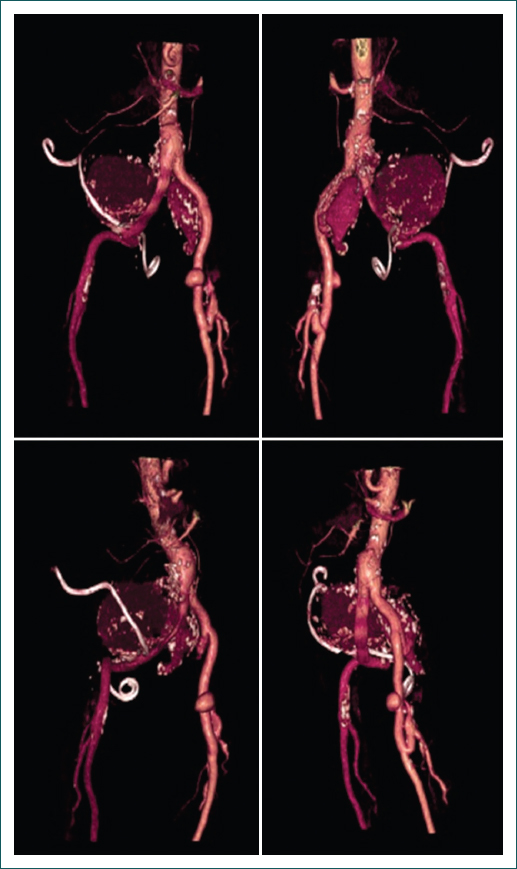

Su padecimiento actual inició 20 días previos a su internamiento, presentando de manera súbita dolor de tipo punzante, intermitente, localizado en la fosa renal derecha, inicialmente de intensidad 4/10 y que aumentó de manera progresiva a 10/10, que irradiaba a la extremidad inferior homolateral, sin exacerbantes ni atenuantes, y acompañado de disuria y polaquiuria. Acudió al urólogo, quien solicitó una tomografía computada contrastada abdominal y pélvica, que evidenció tres aneurismas localizados en las arterias ilíacas común derecha e interna y externa izquierdas, además de quistes renales bilaterales de predominio derecho (Fig. 1).

En la exploración física se encontró hipertenso (140/100 mmHg), con dolor abdominal a la palpación media y profunda en hipogastrio y mesogastrio irradiado al miembro pélvico, con sensación de masa pulsátil y soplo en la misma región e irradiado al flanco derecho, hiperalgesia en la región inguinal derecha y con pulsos periféricos de miembros inferiores disminuidos en intensidad, sobre todo del lado derecho. Se le realizó una angiotomografía, la cual corroboró tres aneurismas: uno en la arteria ilíaca común derecha de 10 × 9 cm con trombo mural, y los otros dos en las arterias ilíacas interna y externa izquierdas, de 5 × 5 cm y 3 × 2 cm, respectivamente; además de quistes renales bilaterales de predominio derecho y litiasis renal, lo que explica las manifestaciones urológicas (Fig. 2).